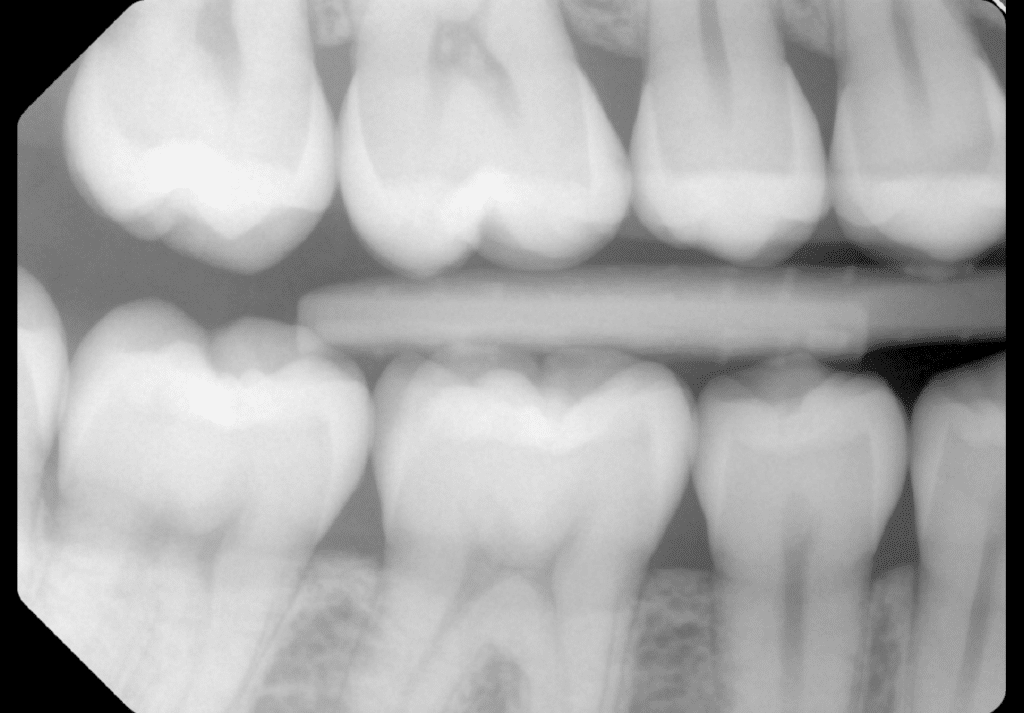

Bitewings med digital sensor

Bitewings er røntgenbilleder taget i hver side af din mund med fokus på mellemrummene mellem dine tænder. Det er her caries oftest udvikler sig enten som et hul i kanten af en gammel fyldning eller på en tandflade der ikke tidligere har været angrebet. På bitewings ses caries i et noget tidligere stadie end hvis vi blot holder os til kun at lave den regelmæssige undersøgelse. Det er der flere fordele ved. Dels kan vi vejlede dig med en grundigere renhold i området, så du med et begyndende hul, kan undgå boret på sigt. Bland andet ved at behandle med Duraphat, som klistre til tanden og indeholder en meget høj mængde fluor, som er med til at bremse videreudvikling af caries. Desuden kan sekundær caries (caries i kanten af en fyldning) og primær caries (et helt nyt cariesangreb) opdages tidligere på det svært tilgængelige sted.

Generelt kan siges at caries der er i et stadie der endnu ikke ses klinisk i din mund, men som ses på bitewings i tandmellemrum, forårsager mindre tab af din tandmasse, og derved forbedre din tands prognose i det lange løb.

På bitewings kan vi også se hvordan dit knogleniveau er med henblik på om du har parodontose. Egentligt kan du sige, at røntgen lader os se alt det der ikke kan ses med vores øjn, når vi kikker ind i munden. Og tit er det netop de ting der ikke ses, som er de vigtigste at opdage. Derfor er røntgen et meget vigtigt og nødvendigt redskab i en moderne tandlæge praksis.